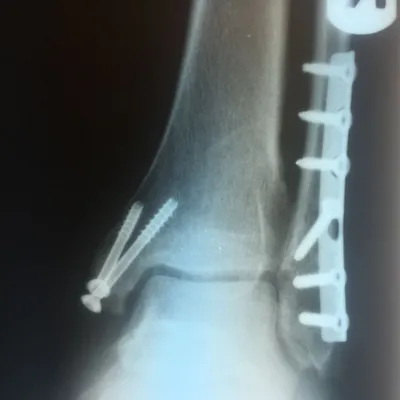

Both the lateral and medial malleolus with fractures with the lateral malleolar fracture classified as a Weber B (at the level of the ankle joint) and the medial malleolar fracture almost transverse (Left x-ray). This is indicative of a Supination External Rotation (SER IV) injury. The fractures are repaired using open reduction with internal fixation (ORIF) technique and fixated with screws and a surgical fractue plate located at the fibular (Right x-ray).

A bimalleolar fracture is a fracture of the ankle that involves the lateral malleolus and the medial malleolus. Studies have shown that bimalleolar fractures are more common in women, people over 60 years of age, and patients with existing comorbidities. Surgical treatment will often be required, usually an Open Reduction Internal Fixation (ORIF). This involves the surgical reduction or realignment of the fracture followed by the implementation of hardware to aid in the healing of the fracture. Usually a plate and screws will be used on the fibular fracture and screws, screws and pins, pins or tension band will most commonly be used on the medial malleolus fracture. A bimalleolar "equivalent" fracture is a fracture of the fibula with rupture of the superficial and deep portion of the deltoid ligaments leaving the medial malleolus intact. Surgical management is common due to the instability of the fracture and displacement of the talus laterally.

Below is the same patient seen above after surgical repair with open reduction and internal fixation with screws for the medial malleolar fracture and screws and plates for the lateral mallolar fracture. Note the even joint spacing across the ankle mortise after correction (left) that is not evenly spaced in the pre-surgical picture (above right).

Pre and Post Op X-rays of Bimalleolar Fracture Fixated with Plate and Screws